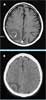

Results of polymerase chain reaction (PCR) testing for Cytomegalovirus were negative. Cerebrospinal fluid (CSF) evaluation revealed normal pressure; a protein level of 42 mg/dL; a glucose level of 88 mg/dL; and a white blood cell count of 1 per high-power field. Results of Gram staining for organisms were negative, and results of PCR testing for Epstein-Barr virus, Cytomegalovirus, and Toxoplasma were negative. CSF cytology did not reveal any malignant cells. An MRI scan of the brain showed a ring-enhancing lesion in the right occipital lobe.

Neuroradiological studies are usually sensitive for primary brain lymphomas but do not establish a definitive diagnosis. Characteristically, 1 or 2 lesions are visible on CT or MRI; lesions are located deep in the brain near the lateral ventricles, and they occur most often in the white matter rather than the gray matter. On CT, the lesions may enhance after administration of contrast. MRI scanning is more sensitive. However, definitive diagnosis requires brain biopsy.